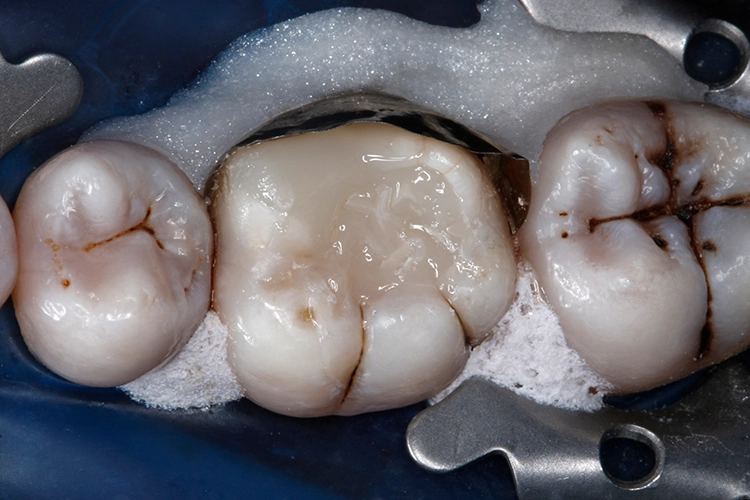

Nachfolgend wurde mit dem nächsten Inkrement VisCalor das restliche Kavitätenvolumen (maximale Schichtstärke: 2 mm) komplett aufgefüllt (Abb. 21). VisCalor kühlt innerhalb weniger Momente nach Kontakt mit dem Zahn durch Wärmeleitung (Konduktion) schnell wieder auf Mundhöhlentemperatur ab und nimmt somit wieder eine hochviskose Konsistenz an (Abb. 22), die eine Modellation der Kauflächenanatomie erleichtert.

Nach Abnahme des Kofferdams wurde die höckerersetzende direkte Kompositrestauration sorgfältig mit rotierenden Instrumenten (okklusal) und abrasiven Scheibchen (lingual) ausgearbeitet. Danach wurde mit diamantimprägnierten Silikonpolierern (Dimanto, VOCO) eine glatte und glänzende Oberfläche der Restauration erzielt.